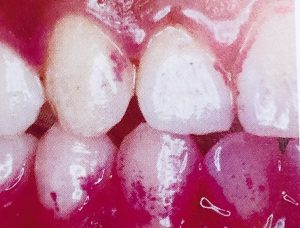

歯肉炎は歯肉が赤みを帯び腫脹が歯肉に限局し、歯周組織の破壊が見られないものをいいます。

歯周病にかかると、歯周組織には肉眼的な臨床所見として、歯肉の発赤、腫脹、歯周ポケットからの出血、排膿、歯の動揺、移動、歯肉退縮、バイオフィルムの付着、歯石の歯面への付着などが見られます。

バイオフィルムが歯面に存在すると、生体の防御反応によって周囲の歯肉に炎症が生じます。

炎症による症状は、発赤、腫脹、疼痛、熱感、機能障害といった、いわゆる炎症の5大兆候と言う形で現れます。

歯周病になった場合は、発赤腫脹が代表的な症状となります。